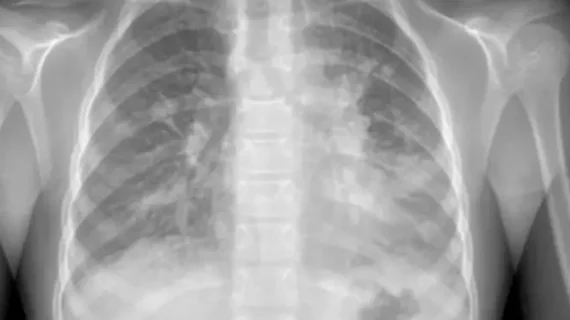

Medical X-rays have mostly converted from film, to computed radiography (CR) that used individual plates to record each X-ray digitally that then had to be uploaded into a PACS, to what is the standard-of-care today with digital radiography (DR). DR X-ray which allows immediate digital transfer of images into a PACS for immediate review. X-rays are used to diagnose fractures, bone abnormalities, lung pathologies and tumors, as well as monitor pediatric growth, plan for surgery and treat oncology patients during radiation therapy. More detailed anatomical imaging, especially soft tissue imaging, is usually sent for advanced imaging with CT or MRI. X-ray, especially mobile DR systems, are a primary use case for artificial intelligence (AI) integration.